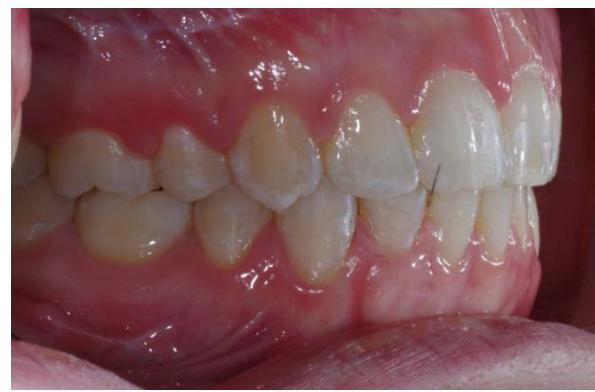

L'examen endobuccal montre une supraclusion incisive, une DDM et un sens transversal correct. Dans le sens sagittal, on note une classe Il dentaire.

Examen endobuccal